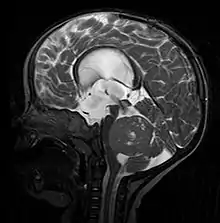

![]() Imagen típica de un meduloblastoma. Resonancia magnética secuencia T2WI de un niño. | ||

La mayoría se visualizan como una lesión sólida que realza con contraste al realizar la tomografía axial computarizada (TAC) o resonancia magnética (RMN) aunque el aspecto puede variar y verse algo difuso principalmente en niños menores de 3 años. La localización del tumor suele ser sobre la línea media del cuarto ventrículo (localizaciones laterales suelen ser más común en adultos). Es muy probable que se observe de hidrocefalia. Su principal diagnóstico diferencial al valorar las imágenes es el ependimoma.

- RMN cerebral: T1WI: hipo a isointenso; T2WI: heterogéneo por tumor quístico, vasos y calcificaciones. Contraaste: marcada hiperintensidad.